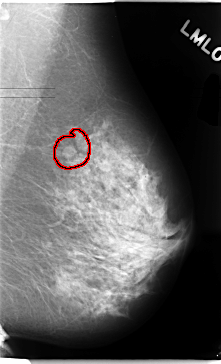

FILE: C_0102_1.RIGHT_MLO.OVERLAY

TOTAL_ABNORMALITIES 1

ABNORMALITY 1

LESION_TYPE MASS SHAPE IRREGULAR MARGINS SPICULATED

ASSESSMENT 5

SUBTLETY 5

PATHOLOGY MALIGNANT

TOTAL_OUTLINES 1

BOUNDARY